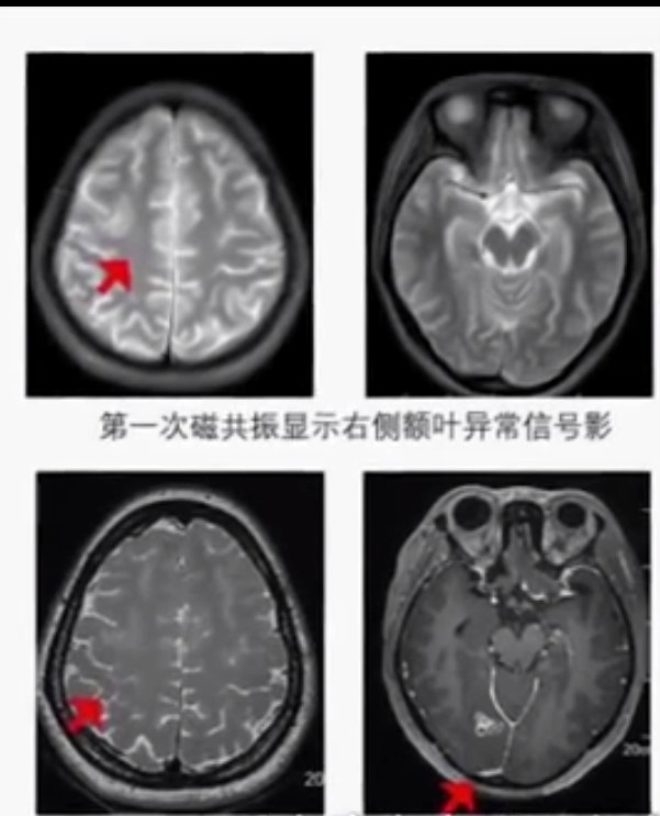

Çin'de 23 yaşındaki bir genç, el ve ayaklarındaki uyuşukluğun arttığını hissedince doktorda soluğu aldı. İsmi Chen olarak açıklanan genç hastanede 17 yıldır beyninde canlı bir kurtçukla yaşadığı ve kurtçuğun beynini yemeye başladığını öğrendi.

Çin'de 23 yaşındaki ismi Chen olarak açıklanan genç, beyninde canlı kurtçukla 17 yıl yaşadı. Altı yaşından itibaren el ve ayaklarında uyuşukluk hisseden Chen, vücudunun üst sağ kısmındaki hislerini kaybedince doktora gitti.